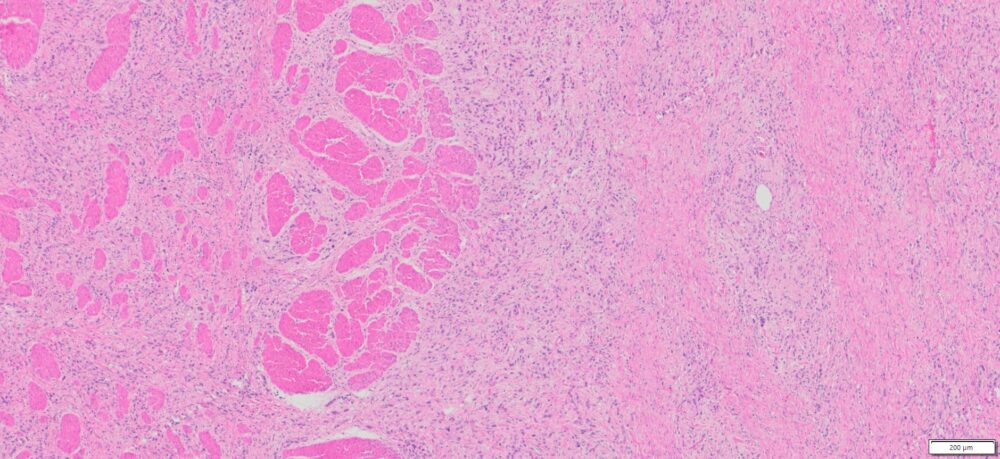

| Organ& Tissue | Pathology Diagnosis | Gender/Age | % Tumor Area | Grade | TMN Stage | Biomarkers |

| Human stomach | Poorly differentiated adenocarcinoma of the stomach | Male/52 | 10% | III | T3N3bMo |